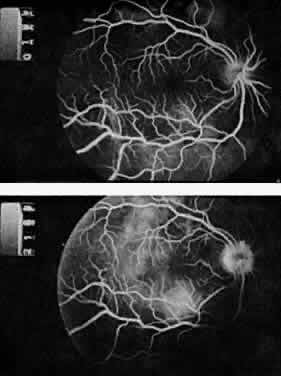

The classic ocular finding in DIC is serous retinal detachment64,65 (Fig. 5). The pathogenesis of these detachments involves choriocapillaris occlusion resulting in retinal pigment epithelial damage and subsequent loss of retinal pigment epithelial barrier and pump function. Fluorescein angiography confirms this pathophysiology, showing delayed filling of the posterior choroid with later pigment epithelial staining (Fig. 6). If the underlying DIC can be reversed, the retina may reattach, with return of vision. Other findings associated with DIC include retinal and vitreous hemorrhages.

Fig. 6. Delayed choroidal filling with pigment epithelial staining in disseminated intravascular coagulation. (Hoines J, Buettner H: Ocular complications of disseminated intravascular coagulation [DIC] in abruptio placentae. Retina 9:107, 1989.)